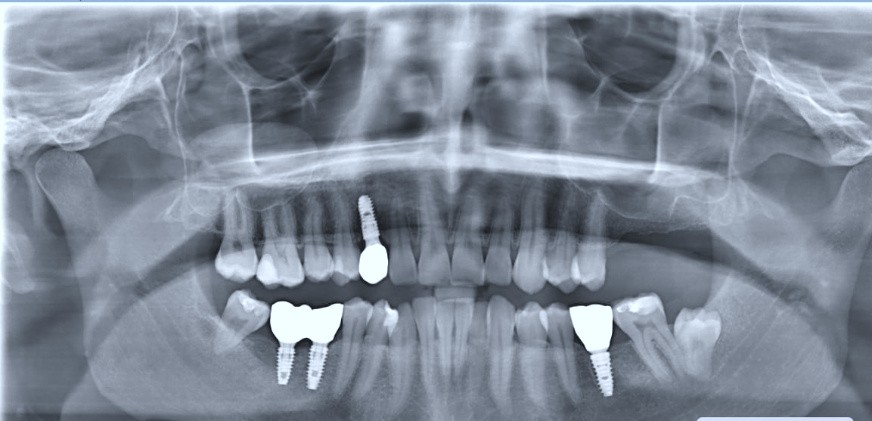

Which of the following is true regarding the following panoramic radiograph?

Which of the following is true regarding dental implant at site 2.6?

Which of the following is true regarding dental implant at site 3.6?